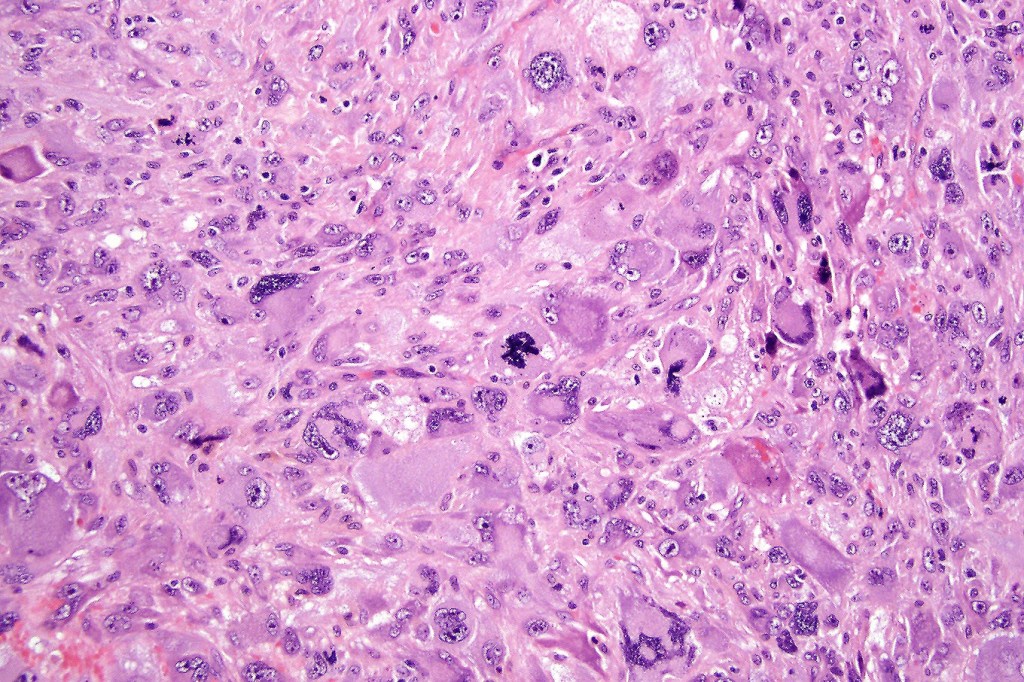

•Admixture of squamous carcinoma & pleomorphic spindled cell, osteoid, chondroid, MFH-like +/- osteoclast-like giant cells & rarely, smooth muscle, skeletal muscle, myofibroblastic or angiosarcomatous elements

•Epithelial component AE1/AE3, CK5/6 & p63 +ve;

•Mesenchymal element variable CD10, CD68, CD99 & lineage specific markers +ve; scattered cells may show weak keratin expression